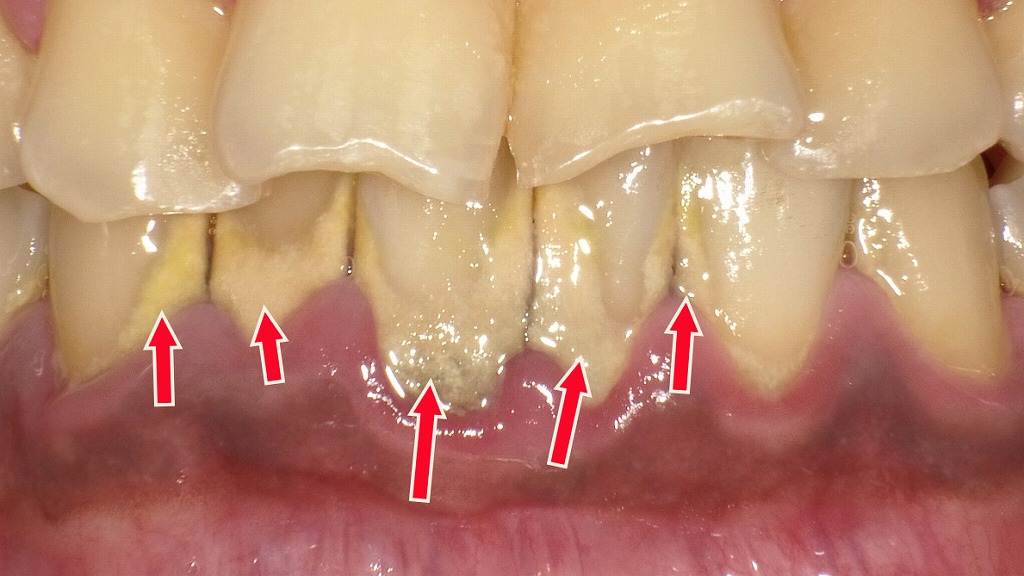

深い歯周ポケットが形成された状態 ― 重度歯周病の口腔内所見

赤矢印で示す部位では、歯ぐきの炎症が慢性化し、歯と歯ぐきの間に深い歯周ポケットが形成されています。これは重度歯周病に特徴的な所見で、歯槽骨の吸収が進行し、細菌や歯石が内部に溜まりやすい状態です。歯周ポケットが深くなるほどセルフケアでは清掃が困難となり、歯の動揺や膿の排出、最終的には歯の喪失につながるリスクが高まります。専門的な歯周治療が不可欠な段階です。